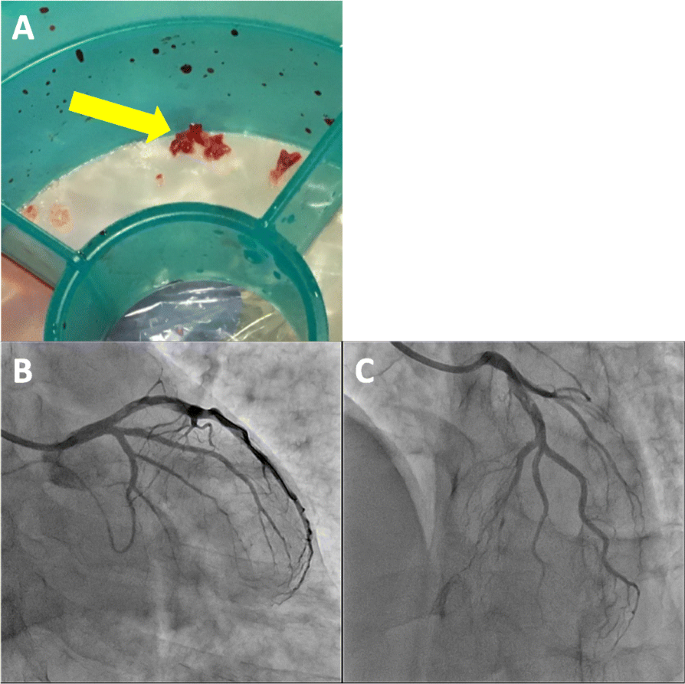

A 49-year-old Japanese man had splenic infarction with unknown cause 2 years ago. He had continued to take warfarin as anticoagulant therapy, but stopped taking the medication as self-judgment several months ago. He had no classical arteriosclerosis factors (hypertension, dyslipidemia, diabetes mellitus, and smoking status). He had sudden-onset rest chest dorsalgia and was transported to our hospital. Immediately after arrival, his pain temporarily improved. On initial examination, his blood pressure was 130/83 mmHg, pulse rate 110 beats/min, respiratory rate 30 cycles/min, and oxygen saturation 100% on room air. His physical examination showed a regular heart rhythm and no murmur, normal respiratory sounds in both lungs, and no edema in his lower extremities. On initial laboratory test, his high-sensitivity troponin I level was 1453.1 pg/mL (normal range: 0.0–26.2), creatinine kinase (CK) 261 U/L (59–248), CK-MB 26 U/L (0–6), platelets 31.5 × 104 /μL (15.8–34.8 × 104), fibrinogen 237 mg/dL (190–390), and D-dimer 1.7 μg/ml (0–0.9). Initial electrocardiography showed normal sinus rhythm and no ST-T change. Transthoracic echocardiography revealed normal wall motion and no asynergy. Contrast computed tomography (CT) showed a small PE and no aortic dissection (Fig. 1a, b). However, he complained of chest pain again following CT. Emergent coronary angiography (CAG) showed no severe stenosis in the right coronary artery and left circumflex artery, but a large thrombus with Thrombolysis In Myocardial Infarction (TIMI) grade 3 flow from the proximal to mid portion of the left anterior descending (LAD) artery (Fig. 2a-c). A 7-Fr guiding catheter was advanced through the left radial artery to the left coronary artery ostium, and a guidewire was advanced to the distal LAD artery. Near-infrared spectroscopy–intravascular ultrasonography (NIRS–IVUS) showed a large amount of thrombus from the proximal to the mid LAD artery, and the max lipid core burden index (LCBI) was 81 (Fig. 2d). Thrombectomy was performed using a 7-Fr aspiration catheter (Fig. 3a) and intracoronary thrombolysis by urokinase 60,000 U. Angiography and NIRS–IVUS revealed decreased thrombus in the LAD artery (Fig. 3b-c). The procedure was completed at this time because additional angioplasty with or without stent was at high risk of slow-flow phenomenon. In the pathological findings, the collected thrombus using an aspiration catheter had many fibrin precipitates. We suspected paradoxical embolism because the ultrasonography revealed a DVT in the bilateral lower leg, but contrast CT and transesophageal echocardiography showed no right-to-left short circuit including a patent foramen ovale, atrial septal defect, and ventricular septal defect, and pulmonary arteriovenous fistula. Further examination of coagulation abnormality revealed hyperhomocysteinemia (total homocysteine level: 140.8 nmol/mL [6.3–18.9], vitamin B12: 121 pg/mL [180–914], folate: 2.3 ng/mL [> 4.0], protein C activity: 111% [70–140], and free protein S: 131.7% [60–150]). Therefore, he was diagnosed with ACS complicated with PE and DVT simultaneously induced by hyperhomocysteinemia. He continued antithrombotic therapy using aspirin, warfarin (his international normalized ratio was controlled from 2 to 3), and heparin (1.5–2.5 times the reference value activated partial thromboplastin time) for 1 week. Peak CK was 347 U/L, and NIRS–IVUS and optical coherence tomography (OCT) revealed decreased thrombus and no significant residual organic stenosis in the LAD artery following 1 week of antithrombotic therapy (Fig. 4a). He was discharged from our hospital continuing antithrombotic therapy with aspirin and warfarin. Follow-up CAG and OCT after 9 months revealed complete thrombus disappearance in the LAD artery (Fig. 5a). His total homocysteine level had decreased to 85.1 nmol/mL by the dietary therapy. He had no cardiovascular event or major bleeding for 1 year.

The collected thrombus using an aspiration catheter and final coronary angiography. The collected thrombus using a repeated aspiration thrombectomy (a, yellow arrow; thrombus). Final coronary angiography revealed thrombolysis in myocardial infarction (TIMI) grade 3 flow and reducing thrombus in the left anterior descending artery (b, c)